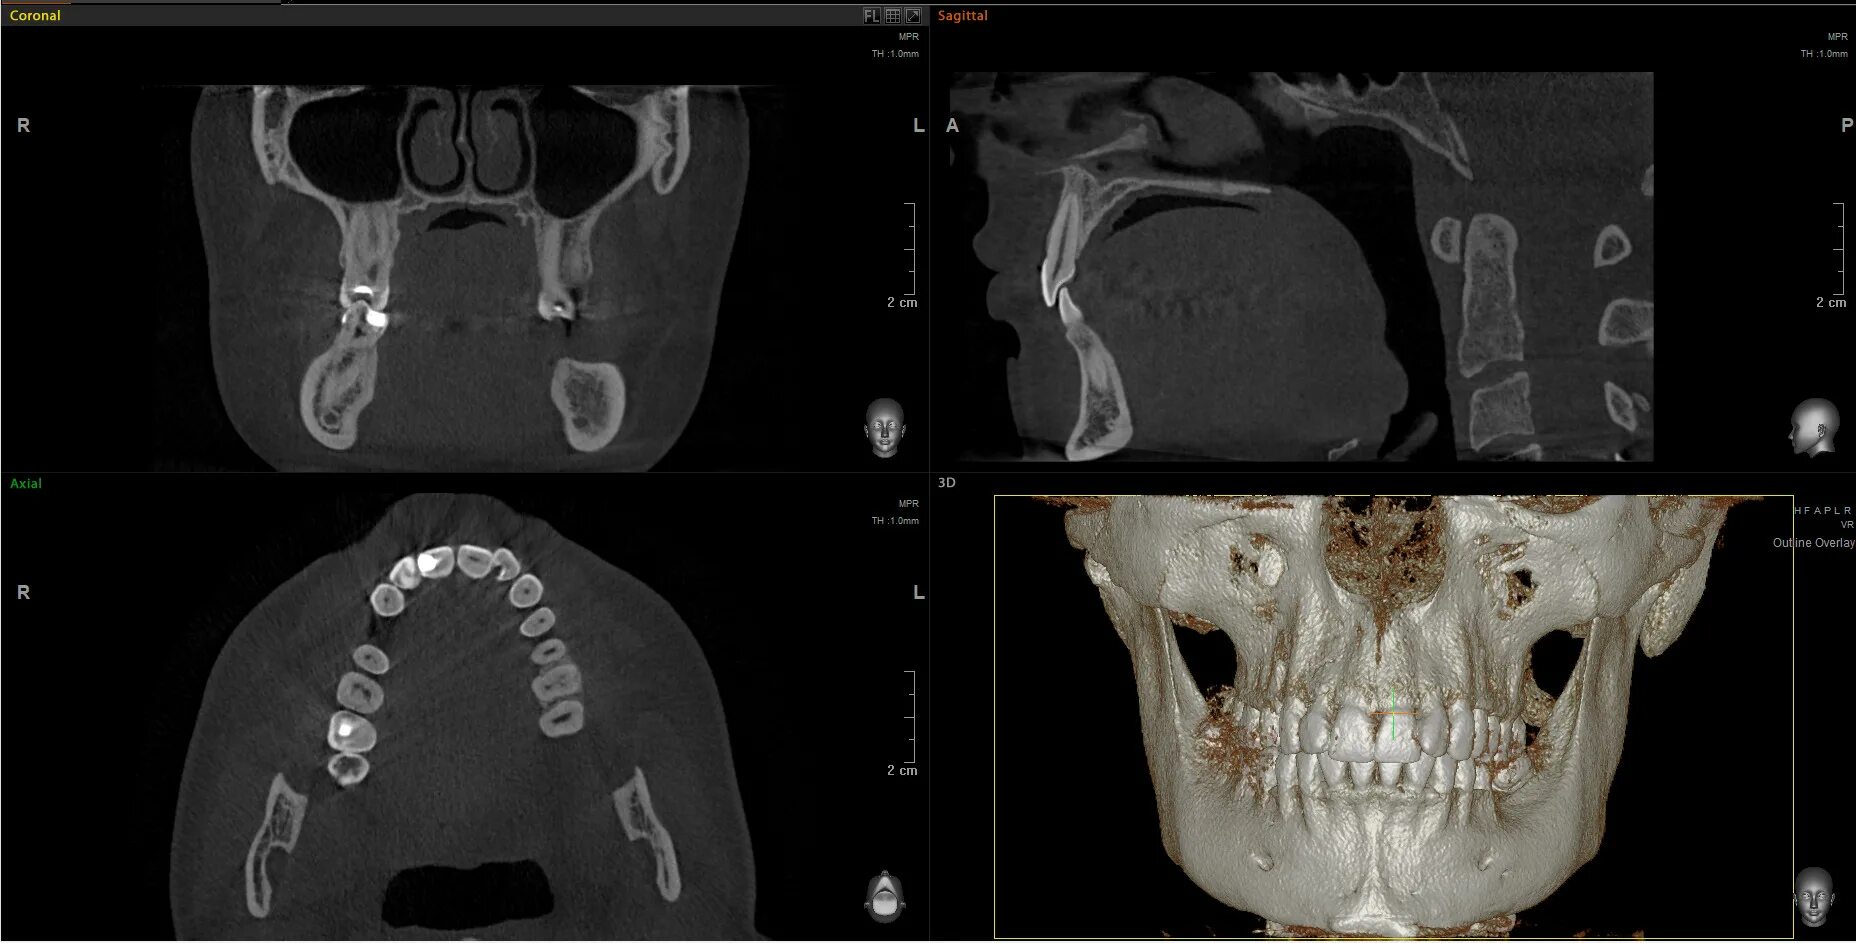

Кл кт